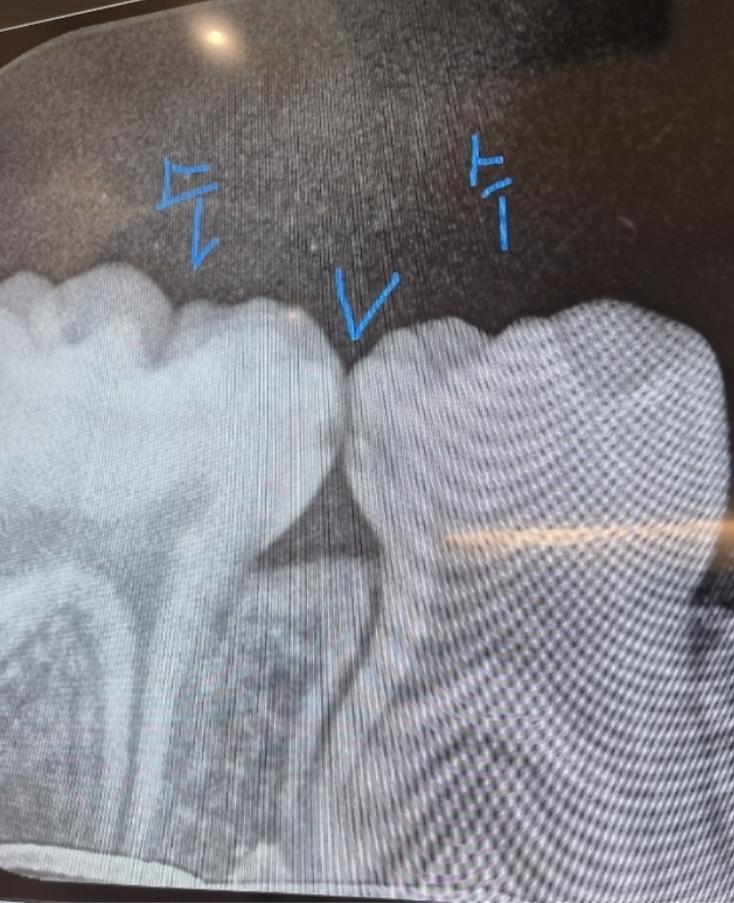

소아 충치 치료 문의드립니다(사진첨부합니다)

헌재 40개월 만3세 아이입니다 치과에 갔다왔더니 충치가 있다고 레진으로 때워야한다고 하더라과요 3개월정도 지켜보면 어떻냐고 하니까 이건 꼭 충치치료해야한다 안하면 신경치료까지 간다고 하는데, 꼭 해야하는게 맞을까요? 만약 해야한다고 한다면 사진상 빨간색원 왼쪽오른쪽 2개를 다 해야하는건지, 아니면 오른쪽만 하고 왼쪽은 지켜보는게 나을지 어떻게 하는게 좋을까요?

5. 또한 방사선 사진상 보이는 옆면 충치는 비교적 빠르게 충치가 진행되기도 하고, 그쪽으로 계속 음식물이 껴서 관리가 더 어렵기도 합니다.

6. 방사선 사진상에서 보이는 충치보다 실제로 충치는 더 크게 진행되었을 수도 있습니다.

방사선사진에서는 인접면에 충치가 있는것으로 보입니다. 아이들의 경우 충치가 쉽게 커질수 있기 때문에 예방적으로 치료를 하는경우가 많습니다.